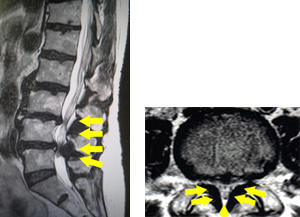

腰部脊柱管狭窄症

どんな病気?

せぼね(脊椎)は7個の頚椎、12個の胸椎、5個の腰椎と仙椎から構成されます。腰椎は主に5つの骨と、間にあるクッションのような椎間板、また神経組織が通っている脊柱管から成り立っています。加齢性変化などにより腰椎の脊柱管が狭くなると、神経組織を圧迫し、下肢のしびれや痛み、脱力などを生じるようになります。この病態を腰部脊柱管狭窄症と言います。中高年における坐骨神経痛の多くは、腰部脊柱管狭窄症によるものです。高齢化とともに年々患者数が増加しており、推定患者数は約580万人と言われています。

検査方法

せぼねの変形や椎間板の傷み具合、不安定性の有無、脊柱管の狭さ、またせぼね全体のバランスなどを見るためにX線検査やCT検査、MRI検査などを行います。進行例では脊柱管の狭さをより詳しく評価するために入院して脊髄造影検査や、同時にどの神経が痛みの原因となっているかを明らかにするために神経の枝に直接麻酔薬を注入する選択的神経根ブロックを行う場合があります。成人期では血管性の下肢の痛みがないか評価するために両手足の血圧を測ったり、骨粗鬆症の有無を評価するために骨密度検査を行うこともあります。